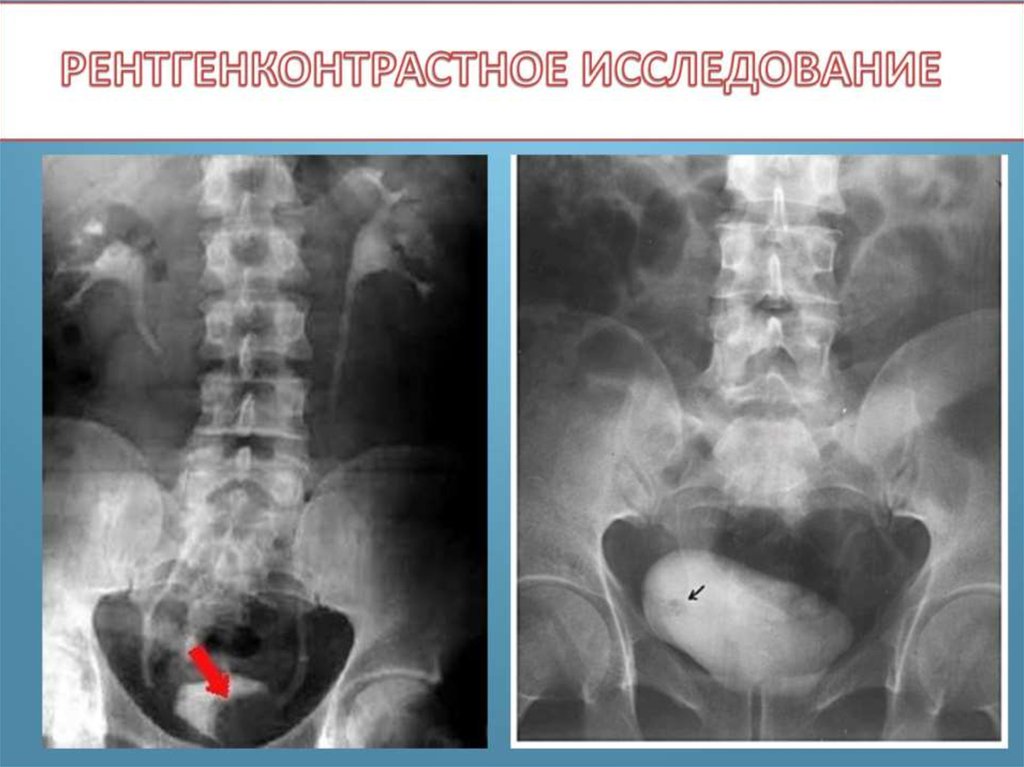

Рак мочевого пузыря